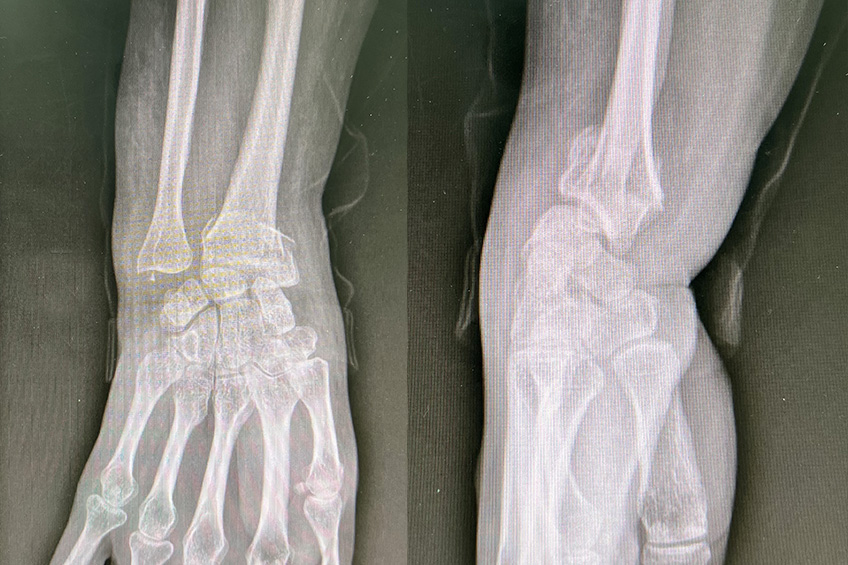

Fracture du poignet

Le diagnostic est guidé par la clinique et confirmé par des radiographies standard qui permettent de mieux évaluer le déplacement de la fracture.

Un scanner peut être nécessaire pour mieux évaluer le déplacement notamment articulaire et anticiper des lésions ligamentaires associées.

En fonction du déplacement observé à la radiographie, ces fractures peuvent nécessiter un traitement chirurgical.

Plusieurs techniques coexistent, avec une nette prévalence des ostéosynthèses par plaque vissée antérieure pour ces fractures.